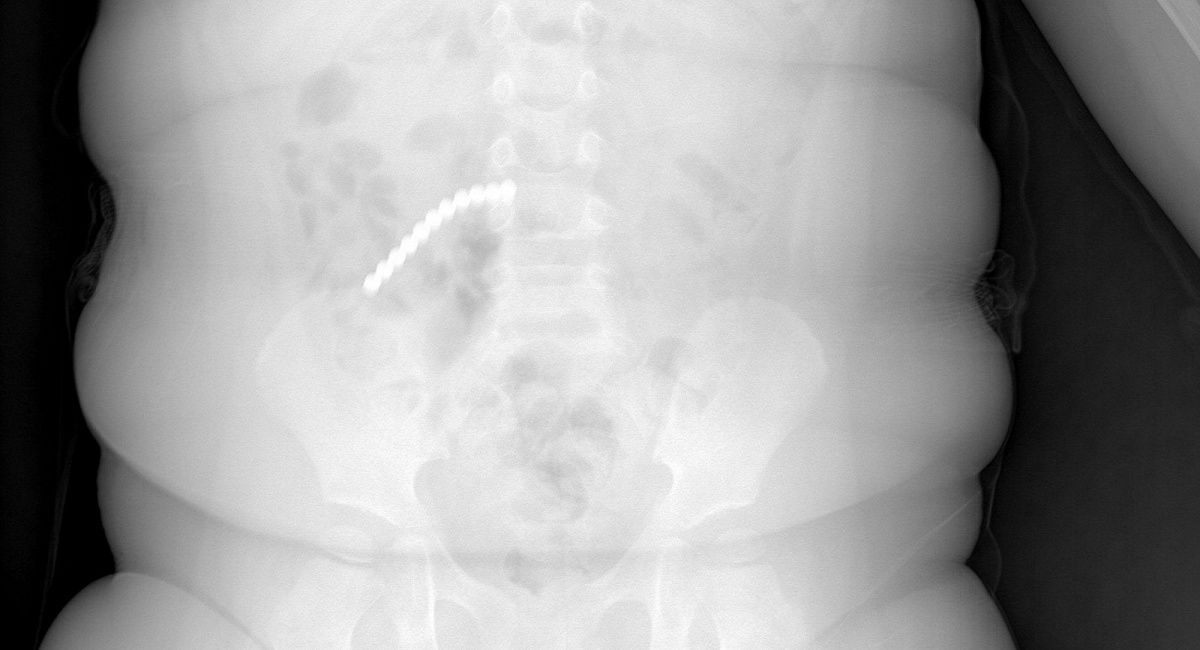

Неокубы опасны для детей: в Бурятии двухлетний малыш проглотил 20 магнитных шариков

Ребенку пришлось перенести сложнейшую операцию – удален аппендикс и участок кишки.

Медики ДРКБ настаивают: подобные магнитные игрушки не должны даже находиться в руках детей, так как несут прямую угрозу их жизни. Они могут привести к летальному исходу, предупреждают в детской больнице.